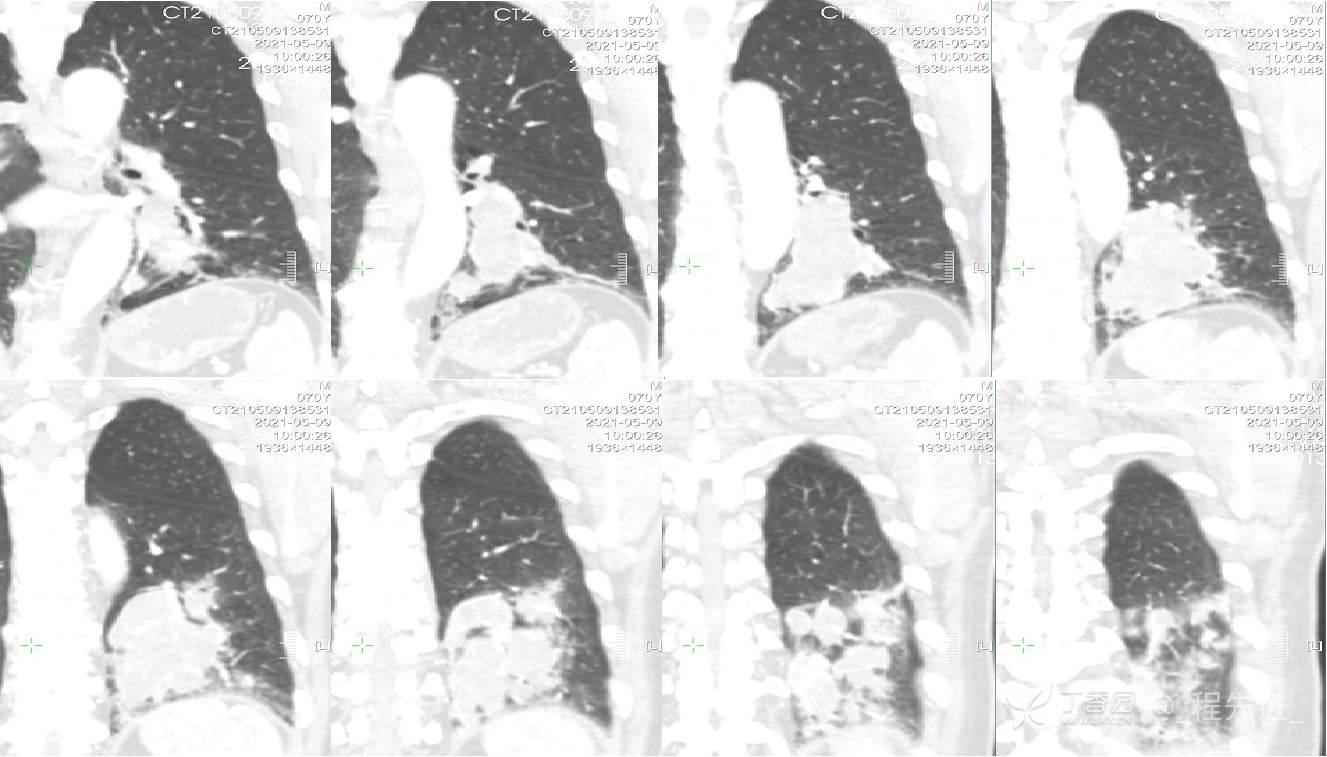

患者性别:男

患者年龄:70岁

简要病史:咳嗽不适1月余,痰中带血7天,胸片发现左肺下叶占位直接做CT增强扫描